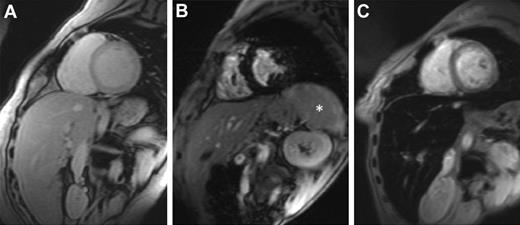

MRI is more widely available, and it offers noninvasive estimation of LIC. MRI scanners generate images of organs in which the signal seen depends on iron concentration. Iron causes the organ to darken more rapidly (Figure 1). T2* is the time needed for the organ to lose approximately two-thirds of its signal and is measured in milliseconds (ms). T2* shortens as iron concentration increases. Its reciprocal, 1000/T2*, is known as R2* and is measured in units of inverse seconds (S−1).

Cardiovascular magnetic resonance T2* images showing the heart and liver from 3 different patients at the same echo time (10.68 ms). (A) Normal appearance with a bright myocardial and liver signal indicating that there is no significant cardiac or hepatic iron loading (myocardial T2* 29 ms, liver T2* 22 ms). (B) Dark myocardial signal indicating severe myocardial siderosis (heart T2* 6.2 ms) but no liver iron (liver T2* 18 ms). *The spleen also has high signal, suggesting that there is no significant splenic iron loading. (C) Normal myocardial signal (heart T2* 24 ms) but dark liver consistent with severe hepatic iron overload (liver T2* 1.8 ms). Images courtesy of Dr J. P. Carpenter (The Royal Brompton Hospital, London, United Kingdom).